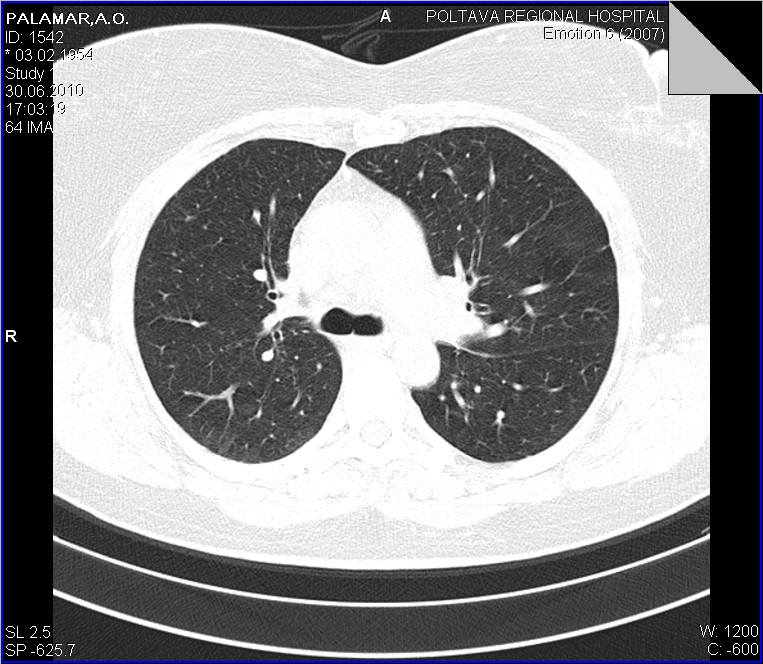

Беседую с пациенткой...да кишечные проблемы были, уже прошли...около 6-8 ми месяцев назад болеела (основная жалоба - кашель), лечилась, в т.ч. стационарно, обследовалась, в т.ч  КТ в ООД - сказали все нормально...живите мол и дальше. Данные предыдущих исследований обещают доставить с понедельника, будем и сами ее докручивать. Ваше мнение, коллеги?

Повторюсь еще раз со сканами, несколько полнее. Конечно, это уже не столь принципиально, но, как по мне, ни С6, ни средней доли нет...Давайте просмотрим еще раз.

Со сканами-то ясность полная. Нет бронха средней доли и шестого. Метод, конечно, превосходный, но и качество снимков имеет огромное значение.

1.Плеврит, как рабочий диагноз тоже пристутсвовал

2. Никтои не спорит, что он, в какой то мере есть, о незначительном количестве "густой" жидкости говорят и УЗИсты

3. Но куда деть "культю" промежуточного бронха? и при чем тогда тут (по отношению к культе) плеврит? Неужели он в состоянии сдавить такой бронх?

1. Спасибо за ссылку, одна из "картинок" полностью повторяет выставленной наблюдение. 2. А теперь о "гвозде", который мне забили пять минут назад "между глазиков". После того, как я переколотил всю хирургию, последняя взялась рьяно выяснять все о больной. Имеется у нее рак матки 4-й степени, состоит она на учете в ООД по этому поводу, все остальные изменения вторичные..... Вот такой случай с ургентности...или о приемственности в наше время...